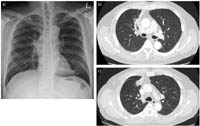

Biểu hiện chính của bệnh được phát hiện ngẫu nhiên trên các hình ảnh chụp X-quang. Tuy nhiên, bệnh nhân có thể trải qua các triệu chứng như ho, ho ra máu, đau ngực hoặc tràn khí màng phổi. Các hình ảnh chụp X-quang của bệnh nang sán phổi khác nhau giữa E. granulosus và E. multilocularis. Bệnh nang sán do E. granulosus,khi các nang chưa bị vỡ, sẽ tạo ra các nốt hoặc khối có bờ mịn và không bị vôi hóa. Ngược lại, loài E. multilocularis gây ra bệnh Echinococcosis phế nang (Alveolar Echinococcosis) và trên hình ảnh chụp X-quang hoặc CT scan, bệnh này xuất hiện dưới dạng các nốt hoặc khối có hình dạng tạo thùy và có sự vôi hóa.

Các đặc điểm chính của nang sán trên hình ảnh X-quang bao gồm: dấu meniscus, dấu bán nguyệt, dấu Cumbo, dấu vỏ hành tây, dấu hoa súng và dấu khối trong khoang. Một trong những dấu hiệu kinh điển trên hình ảnh X-quang của nang sán là một vùng sáng tròn rõ ràng trong phổi, có hoặc không có sự vôi hóa(Hình 6). Bệnh nang sán phổi có thể bị nhiễm trùng thứ phát và trên hình ảnh X-quang ngực có thể xuất hiện u nang và mức dịch khí (Hình 7).

Hình 6.Chụp X-quang phổi thông thường cho thấy có  một vùng sáng tròn rõ ràngnằm ở vùng thấp bên trái của phổi.

|   Hình 7.Hình ảnhX-quang ngực nghiêng cho thấy mức dịch khí bên trong một nang sán đã tồn tại từ trước gợi ý  nhiễm trùng chồng lấn.